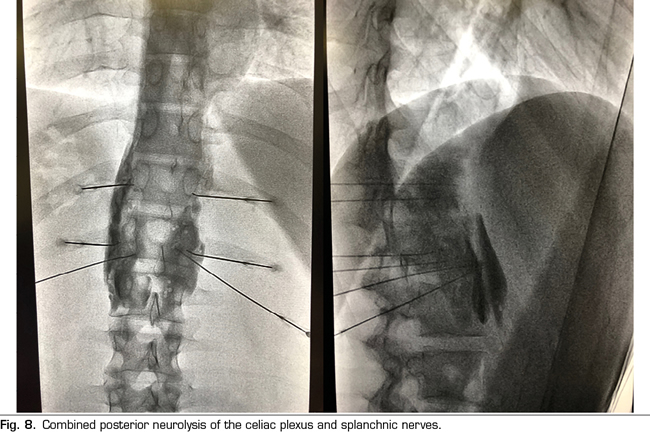

Figure 8